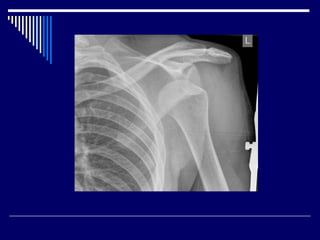

1.Shoulder dislocation

anterior > 95%

posterior 2-4%

inferior (luxatio erecta) < 1%

• #10 shoulder dislocation, there is separation of the humerus from the glenoid of the scapula at the glenohumeral joint. most commonly dislocated large joint.  A number of biomechanical forces can produce shoulder dislocation, including : 1.forced extension, abduction and external rotation most commonly leads to anterior dislocation 2.direct blow from behind leads to anterior dislocation 3.forceful contraction of shoulder girdle muscles uncommon leads to posterior dislocation 4.forced hyperabduction leads to inferior dislocation

• #11 AP and lateral +/- axillary view

• #12 head of the humerus is driven forward from inside the glenoid cavity to a place under the coracoid process. This type of dislocation is sometimes referred to as a subcoracoid dislocation. The joint capsule is usually avulsed from the margin of the glenoid cavity. Anterior shoulder dislocation can also be the result of a detached labrum. When both the labrum and the capsule along the anterior margin of the glenoid cavity are avulsed, the injury is called a Bankart lesion. Compression fracture of the humeral head from the force of hitting the hard glenoid is called a Hill-Sach's lesion. Three-fourths of the patients with a Bankart lesion will also have a Hill-Sach's lesion.

• #13 The humeral head is dislocated anteriorly and inferiorly with the anteroinferior margin of the glenoid, with some flattening of the corresponding part of the humerus.

• #14 An anteroinferior shoulder dislocation is present without associated fracture.